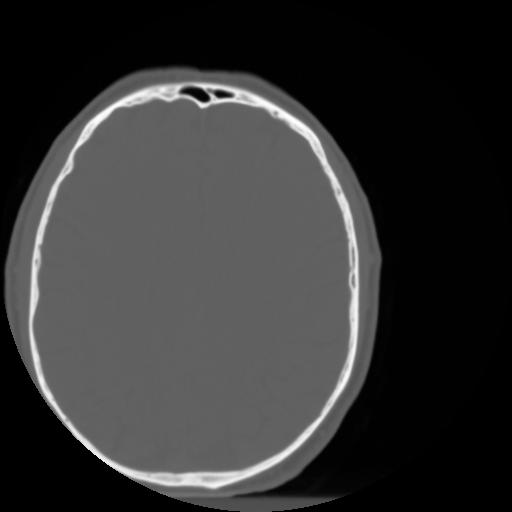

3 CEREBRO,,Axial,3.0,CEREBRO,,